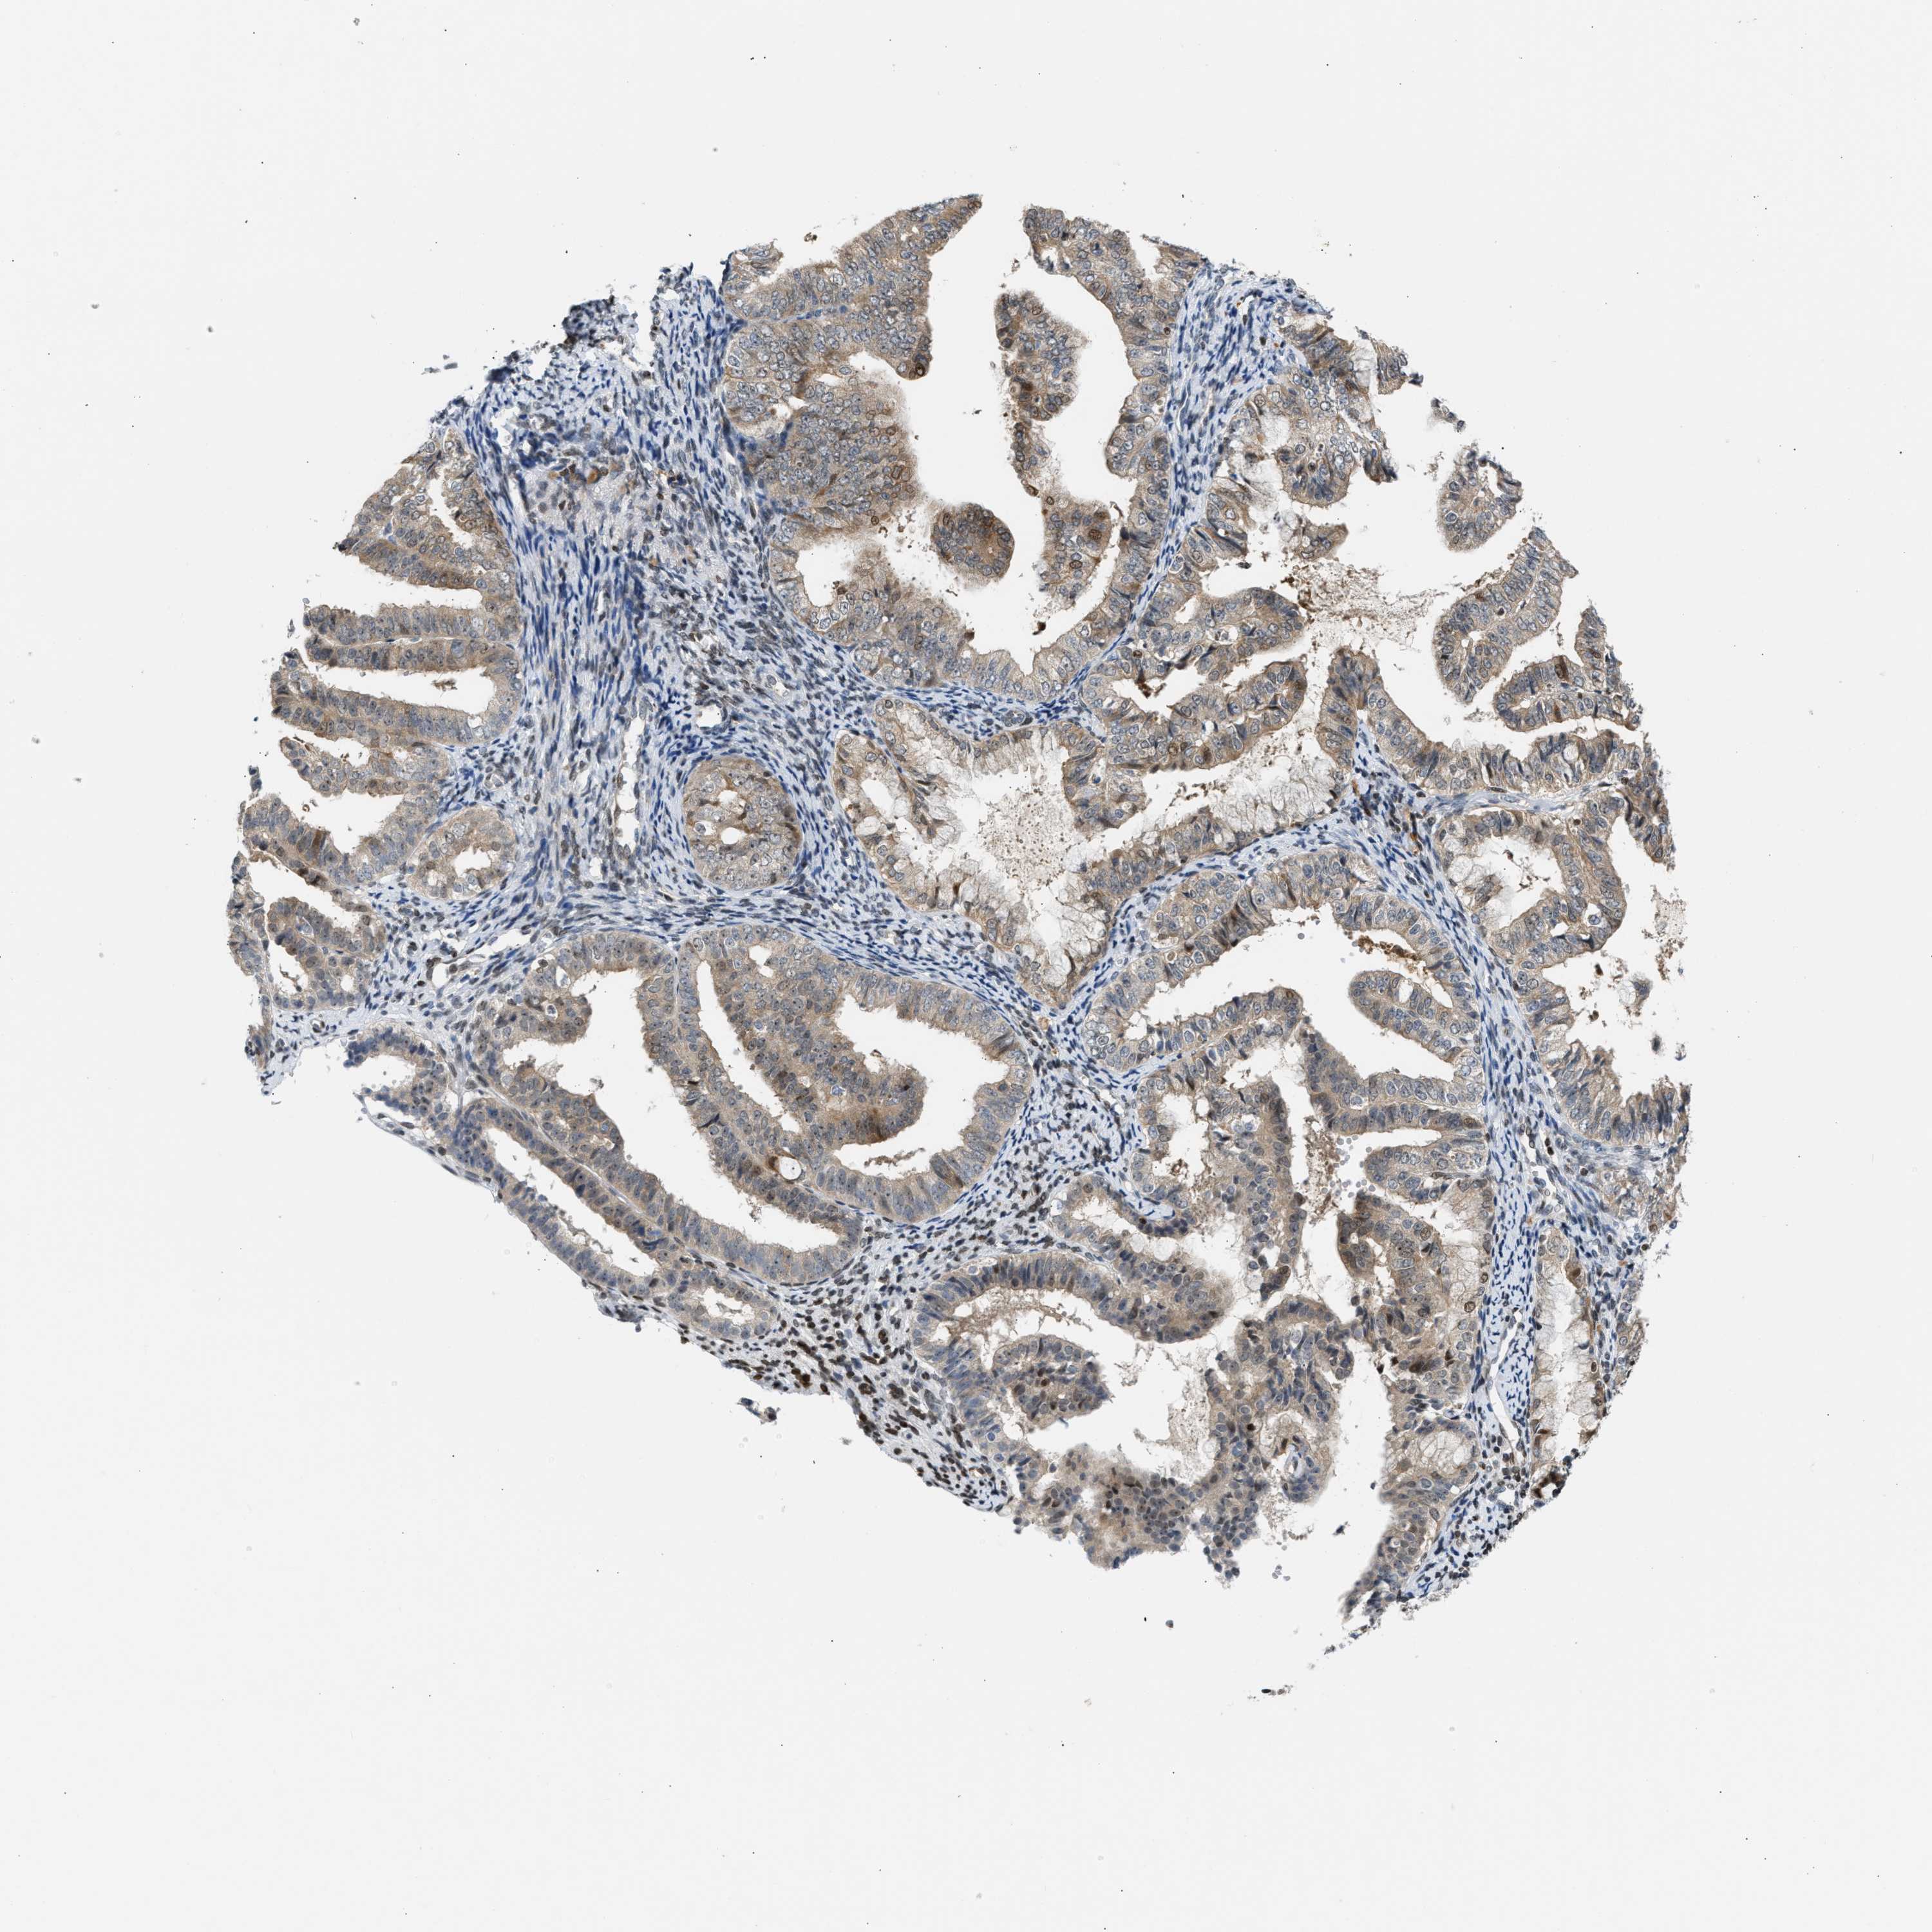

ENDOMETRIAL CANCER - Protein expressioni

A mouse-over function shows sample information and annotation data. Click on an image to view it in a full screen mode. Samples can be filtered based on level of antibody staining by selecting one or several of the following categories: high, medium, low and not detected. The assay and annotation is described here.

Note that samples used for immunohistochemistry by the Human Protein Atlas do not correspond to samples in the TCGA dataset.

Antibody stainingi

Antibody staining in the annotated cell types in the current human tissue is reported as not detected, low, medium, or high, based on conventional immunohistochemistry profiling in selected tissues. This score is based on the combination of the staining intensity and fraction of stained cells.

Each image is clickable and will lead to virtual microscopy that enables deeper exploration of all samples and also displays staining intensity scores, fraction scores and subcellular localization as well as patient and tissue information for each sample.

Antibody CAB020139

Staining

High

Medium

Low

Not detected

Intensity

Strong

Moderate

Weak

Negative

Quantity

>75%

75%-25%

<25%

None

Location

Nuclear

Cytoplasmic/membranous

Cytoplasmic/membranous,nuclear

Adenocarcinoma, NOS